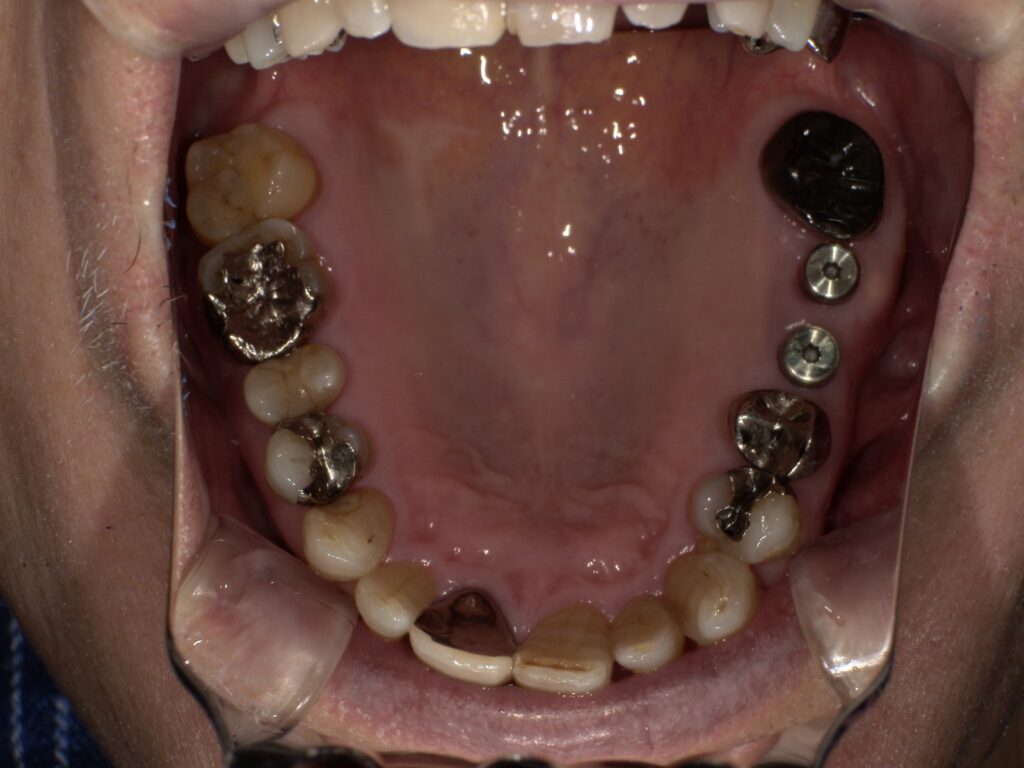

下顎の5番7番にインプラントを埋入した2次オペ後の写真です。

下顎は5番7番相当部にインプラントを埋入し、上部構造はブリッジ形態となっております。

今回は患者様のご希望により、上部構造は銀歯で作成いたしました。